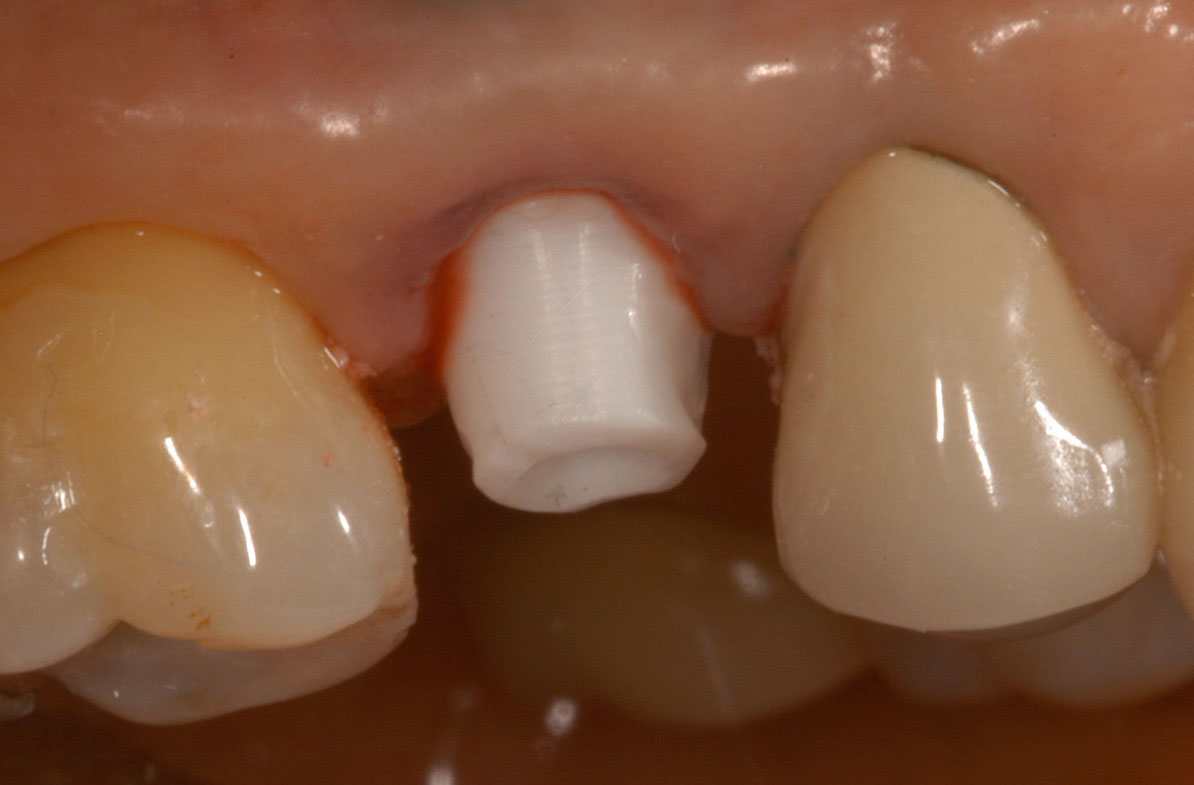

A dental implant most closely replicates natural tooth structure. Once it is osseointegrated, many patients cannot differentiate an implant from a natural tooth. Furthermore, dental implants do not decay or need root canal therapy. Even though the cost is slightly more than a bridge, it is an investment for the future, as implants usually last longer than a bridge. A 10-year report on posterior single implants shows a success rate of 97%.33 Once an implant is placed, the osseointegration and tissue healing time of approximately 4 months is necessary before a final crown is placed. A temporary crown can be placed the same day the implant is placed, but this is only for esthetics, not for function (Figure 15 through Figure 19).

Figure 11 – Internal connection implant system – implant placed post-extraction

Figure 11

Figure 12 – Prefabricated zirconia abutment fitting the internal connection in Figure 11

Figure 12

Figure 13 – Zirconia abutment torque onto implant

Figure 13